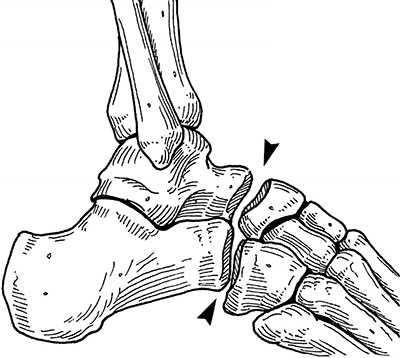

Рис. 1. Сустав Шопара с наружной и внутренней поверхности

Рис. 2. Сустав Шопара по тыльной поверхности стопы. Сустав включает в себя пяточно-кубовидный и таранно-ладьевидный суставы